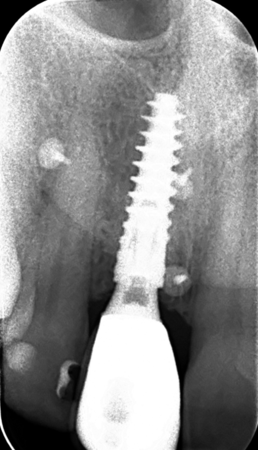

The surgical protocol began with the atraumatic extraction of tooth 1.1 to preserve as much of the alveolar socket as possible. Immediately following extraction, an N1 implant was placed into the socket using a guided surgical approach to ensure ideal three-dimensional positioning. The “one abutment one time” technique was applied to minimize soft tissue manipulation during the healing phase, which is particularly important in esthetic areas.

Given the significant buccal defect, guided bone regeneration (GBR) was performed simultaneously. A mixture of autologous bone and creos™ xenogain™ was applied to the defect and covered with a resorbable creos™ membrane to restore ridge width and support the buccal contour. In addition, a connective tissue graft was harvested and placed in the vestibular region to increase the thickness of keratinized mucosa. This combined approach addressed both hard and soft tissue deficiencies, providing the biological foundation for a stable and esthetic outcome.